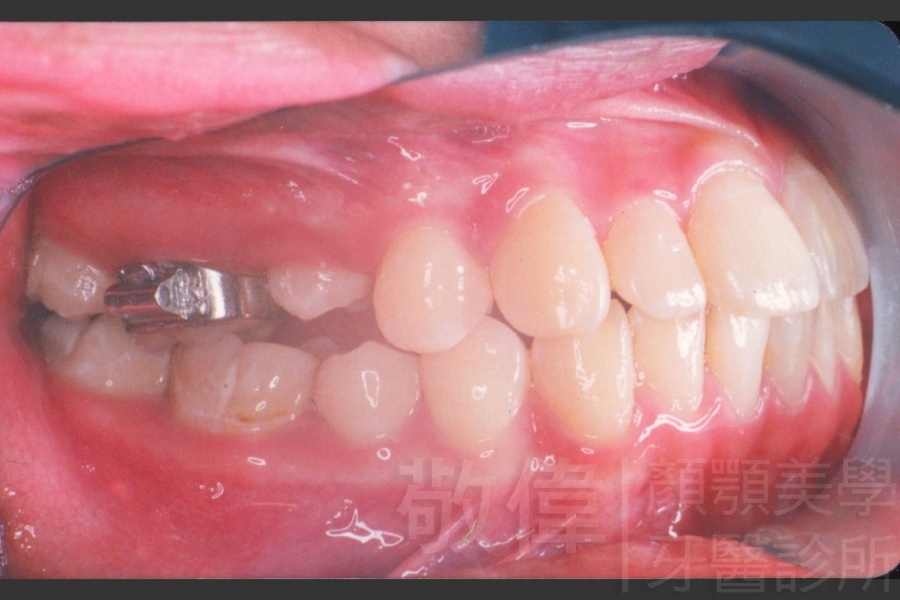

齒顏矯正/戽斗、亂牙、爛牙,變身 免植牙的健牙美女

<個案說明>

變臉矯正,原來戽斗妹跟大歪臉變成自信正妹

經由本院3D數影X光影像儀分析、與3D齒顎顏矯正技術,再配合口腔顎面正顎專科醫師施以正顎手術治療,雙方共同合作,使患者臉部外觀有很好的改善,大歪變小歪,產生了天南地北的大改變,她的人生也整個變得不一樣。

因為矯正與正顎手術的配合,使「戽斗妹」變成了「陽光正妹」,完全的改變了她的人生,在面對各種場合、與人交際都散發出自信微笑。所以,奉勸家長,如果小朋友有臉顎畸型的問題,應該考慮配合做這種簡單、安全、有效的正顎手術。